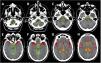

MethodsA consecutive series of SAH patients admitted to a single tertiary centre between 2012–2018, within 72 h of onset, harbouring a single intracranial aneurysm. A semi-automatized method of blood quantification, based on the relative density increase, was applied to initial non-contrast CTs. Five regions were used to define the bleeding patterns and to correlate them with aneurysm location: perimesencephalic, interhemispheric, right/left hemisphere and intraventricular.

Results68 patients were included for analysis. There was a strong association between the distribution of blood and the aneurysm location (p < 0.001). In particular: ACom and interhemispheric fissure (p < 0.001), MCA and ipsilateral hemisphere (p < 0.001), ICA and ipsilateral hemisphere and perimesencephalic cisterns (p < 0.001), PCom and hemispheric, perimesencephalic and intraventricular (p = 0.019), and PICA and perimesencephalic and intraventricular (p < 0.001). The internal diagnostic value was high (AUROC ≥ 0.900) for these locations.